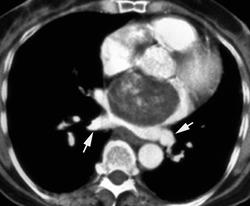

Особенностью рентгенологической картины при миксоме левого предсердия, если нарушения гемодинамики соответствуют митральному стенозу, является отсутствие выбухания ушка левого предсердия, полость левого предсердия расширена меньше, чем при митральном стенозе. При обызвествлении миксомы на рентгенограммах виден каль-циноз.